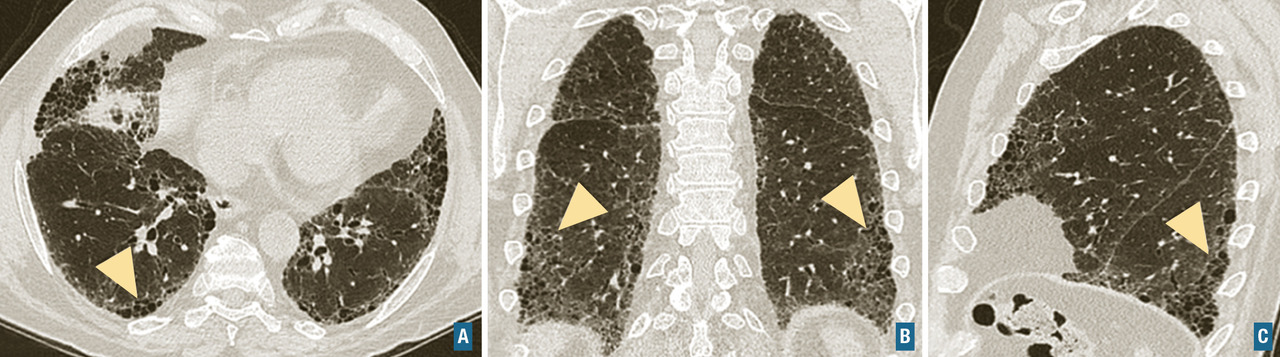

Les symptômes comprennent une dyspnée, une toux, des râles « piaulants » (squeaks) à l’auscultation et parfois des signes généraux semi-retardés : frissons, asthénie, fièvre. Le scanner thoracique met en évidence une atténuation en mosaïque à trois niveaux de densité, des plages de verre dépoli et des nodules flous centrés sur les bronches (fig. 5). Un piégeage aérien est fréquemment retrouvé, et se manifeste par une augmentation du contraste entre zones saines et pathologiques sur les coupes en expiration. Des signes de fibrose sont présents dans les formes fibrosantes. Une lymphocytose > 20-30 % dans le lavage broncho-alvéolaire conforte le diagnostic. L’histologie met en évidence une bronchiolite lymphocytaire, une infiltration interstitielle lymphocytaire, et des granulomes mal définis.

Connectivites

Fibrose pulmonaire idiopathique (FPI) : c’est la plus fréquente et la plus grave des pneumopathies interstitielles diffuses idiopathiques chroniques. Elle est définie par une fibrose progressive et irréversible du poumon, de cause inconnue, et survient le plus souvent chez les hommes dans leur septième décennie, fumeurs ou anciens fumeurs. La médiane de survie après le diagnostic et sans traitement est d’environ 3 ans. Les signes cliniques sont non spécifiques, et incluent une dyspnée d’effort d’apparition progressive, une toux sèche, des crépitants secs, dits « Velcro », précoces et parfois un hippocratisme digital. La fibrose pulmonaire idiopathique est caractérisée par un aspect radiologique et/ou histologique de pneumopathie interstitielle commune. L’aspect scanographique de pneumopathie interstitielle commune associe du rayon de miel, des réticulations sous-pleurales, des bronchectasies et bronchiolectasies de traction (fig. 7). Les anomalies sont de distribution basale et sous-pleurale prédominante, avec un gradient apico-basal. Il existe une alvéolite neutrophilique (10-20 %) ou une discrète éosinophilie au lavage broncho-alvéolaire. Le diagnostic de fibrose pulmonaire idiopathique requiert l’élimination des causes médicamenteuses, d’exposition professionnelle ou domestique et de connectivite, ainsi que la mise en évidence d’un aspect typique au scanner. La biopsie pulmonaire n’est requise que chez les patients dont le diagnostic est incertain et dont la confirmation modifierait l’attitude thérapeutique. L’emphysème fréquemment associé chez les fumeurs modifie la présentation et l’évolution. Il n’existe pas de traitement curatif, la prise en charge actuelle repose sur les médicaments antifibrosants (pirfénidone ou nintédanib) qui ralentissent l’évolution de la maladie. L’évolution clinique peut être émaillée d’exacerbations aiguës accélérant le déclin de la fonction respiratoire et aggravant le pronostic.